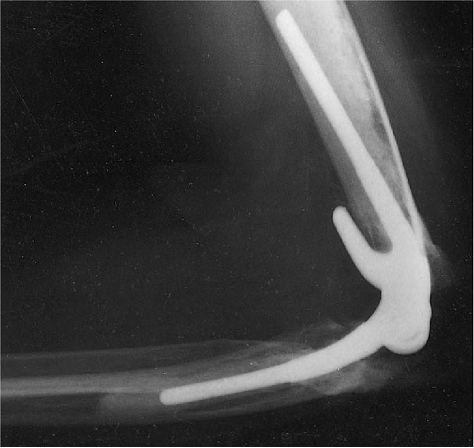

Figure 18-49. Patient with distal humeral nonunion of 2 years’ duration (A). Excellent function persists 4 years after replacement (B).